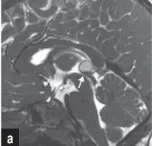

影像学检查显示基本正常,唯独存在一处细微异常。为明确诊断,如如接受了头颅核磁共振检查,但结果并未提供清晰答案,反而增加了医生的困惑。影像评估显示,如如的脑部结构与常人基本一致:中脑导水管形态正常,脑脊液流动未见梗阻,侧脑室宽度也在标准范围内。然而,医生注意到一个细微的异常征象——导水管入口处存在明显狭窄。这一发现究竟提示何种疾病?遗憾的是,尽管识别出这一结构性异常,但结合如如的整体临床表现,多种最初怀疑的疾病可能性都被逐一排除。

这是否意味着所有松果体囊肿都需要手术治疗?在一定程度上,答案是否定的。传统的手术指征通常仅限于囊肿体积增大,引发脑室扩张并导致脑积水的情况。然而,如如的术前临床表现并不符合这一传统标准,她并未出现脑积水征象。那么,施罗德教授决定实施手术的依据何在?在其研究论文《Symptomatic Pineal Cysts Without Ventricular Enlargement》中,施罗德教授明确指出,对于未伴发脑室扩张的症状性松果体囊肿,手术决策需审慎权衡患者的整体状况。既要避免过度手术治疗,也不能因诊断不足而忽视患者的痛苦。因此,他建议当患者出现颅内高压临床表现(如剧烈全头痛、喷射性呕吐)、脑干受压体征,且磁共振成像证实囊肿存在占位效应或导致导水管狭窄时,应及时考虑手术治疗。